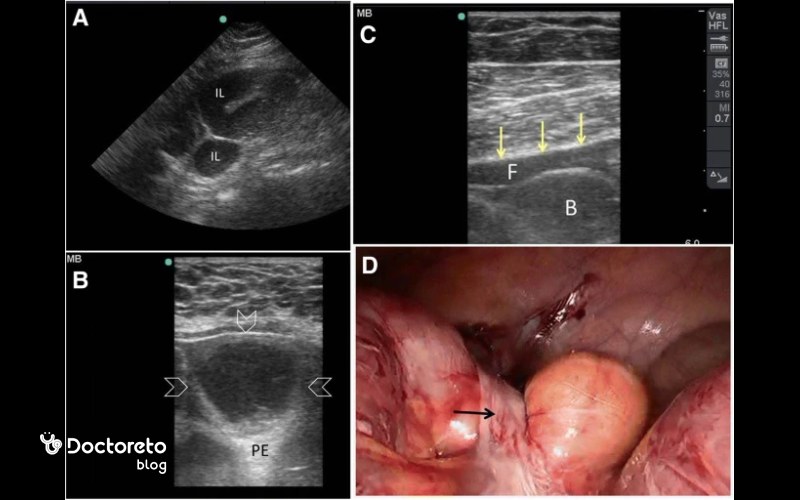

۲. سونوگرافی اندورکتال/اندوآنال

سونوگرافی اندورکتال (EUS) از یک پروب خاص که به داخل مقعد وارد میشود استفاده میکند تا تصاویری با وضوح بالا از دیواره رکتوم و بافتهای اطراف آن به دست آورد. این روش برای تشخیص مرحله سرطان رکتوم بسیار مؤثر است و به پزشکان این امکان را میدهد که عمق نفوذ تومور و گسترش آن به غدد لنفاوی مجاور را بررسی کنند.

تحقیقات نشان دادهاند که EUS حساسیت بالایی برای شناسایی تومورهای مرحله اول رکتوم دارد و در مقایسه با سایر روشهای تصویربرداری برای مرحلهبندی محلی، بهطور خاص مؤثرتر است.